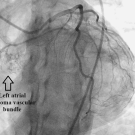

Steven R. Bruhl, MD, MS, FACC1 • Andrew J. Slembarski, MD2 • Gavin N. Sluss3

A 46-year-old woman presented in an outpatient cardiology office for preoperative clearance for tubal ligation surgery. On assessment, the physicians found her to have frequent premature ventricular...